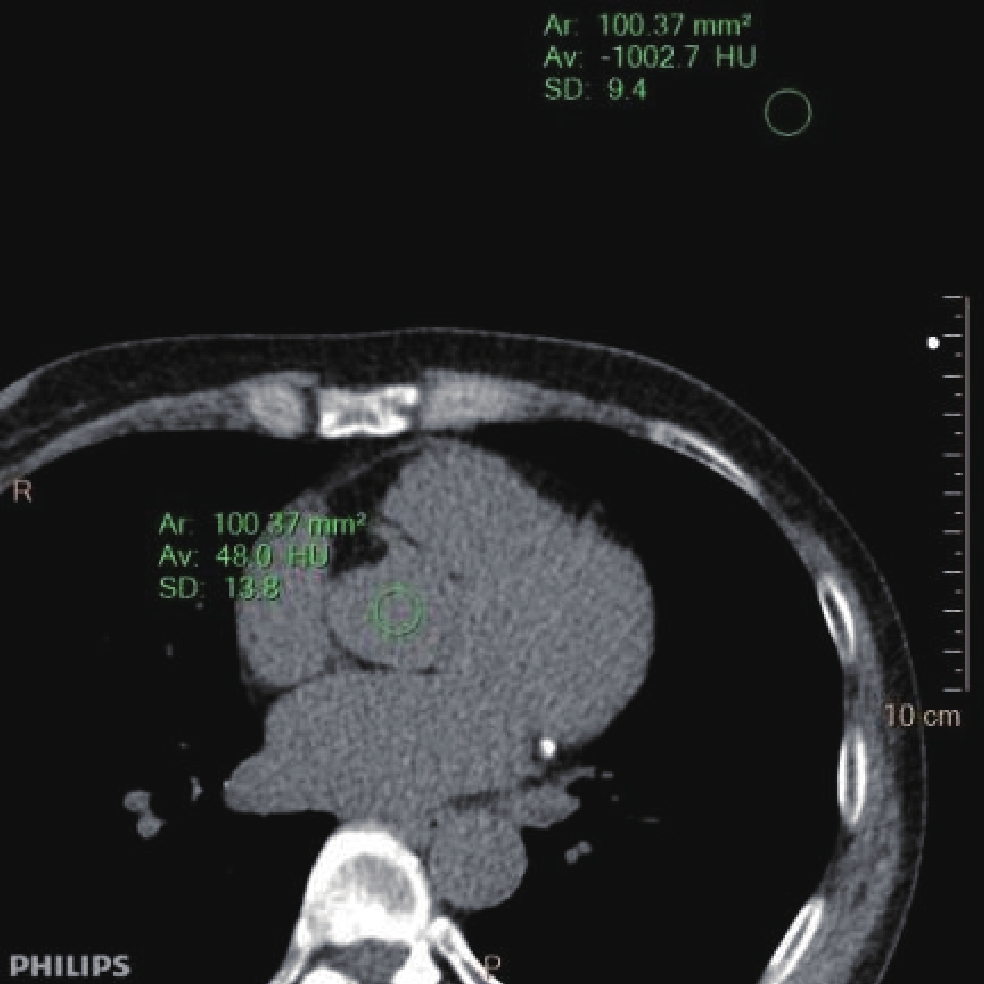

• 摘要: 目的:探讨智能最佳管电压技术SEMI模式(Care kV SEMI)联合迭代算法在冠状动脉检查中钙化积分低剂量扫描成像中的可行性。方法:模体实验采用Care kV SEMI模式和管电流调制技术(CareDose 4D on)。参数设置:SEMI 120 kV(ref.kV分别为100 kV、120 kV),ref.mAs分别为40、60和80 mAs,重建算法分别为滤波反投影算法(FBP)、基于模型的高级迭代算法(ADMIRE)3、4、5。比较各组图像的容积CT剂量指数(CTDIvol)、对比噪声比(CNR)和品质因子(FOM)。回顾性分析30例冠状动脉钙化积分扫描图像作为对照组(ref.kV 120 kV,ref.mAs 80 mAs,重建滤波反投影(FBP)算法),前瞻性采集109例患者冠脉钙化积分CT图像作为实验组(ref.kV 100 kV,ref.mAs 80 mAs,重建算法分别为FBP、ADMIRE 3、5),两组实际管电压均为SEMI 120 kV。记录并计算剂量长度乘积(DLP)、有效剂量(ED)、左主干(LM)和右冠状动脉(RCA)开口层面的CNR、钙化积分(Agatston Score)以及风险分级。由两名高年资诊断医生对患者冠脉图像进行4分法主观评价。对临床研究两组患者冠状动脉CT钙化积分扫描的辐射剂量、钙化积分数值、风险分级以及图像质量差异进行统计学分析。结果:①模体研究结果:实验组辐射剂量较对照组均降低;相同扫描条件CNR 随迭代算法等级增加而增加;ref.kV 100 kV+ref.mAs 80 mAs组4种重建算法下FOM均高于对照组。②临床研究结果:实验组与对照组ED存在统计学差异;实验组FBP和对照组CNR 在LM和RCA两个层面上均无统计学差异;实验组不同重建算法所得Agatston积分间无统计学差异;实验组风险等级Kappa值分别为0.93和0.88,一致性好;两名医生主观评价Kappa值为0.952,实验组与对照组主观评分有统计学差异。结论:BMI 18~25患者进行冠状动脉钙化积分CT扫描时,使用Care kV SEMI模式联合迭代算法对钙化积分和风险分级影响较小,可以有效降低患者辐射剂量。

Abstract: Objective: To explore the feasibility of the SEMI mode of the intelligent optimal tube voltage selection technique (Care kV SEMI) in combination with an iterative algorithm in low-dose calcium score scanning for coronary artery examination. Methods: SEMI mode of Care kV and tube current modulation (CareDose 4D) were used in the phantom experiment. For the SEMI group SEMI 120 kV (ref.kV was 100 and 120 kV), ref.mAs was 40, 60, and 80 mAs. The reconstruction algorithms were filtered back projection (FBP) ADMIRE 3, 4, 5. The volume CT dose index (CTDIvol), contrast-to-noise ratio (CNRp) and figure of merit (FOM) of each group were compared, and a set of parameters were selected for clinical patient image acquisition after a comprehensive comparison. A retrospective analysis of coronary artery calcium score scanning images was conducted, using 30 patients as a control group (ref.kV, 120 kV; ref.mAs, 80 mAs; reconstruction algorithm, filtered back projection, FBP) and a prospective collection of 109 patients with coronary artery calcium score CT images as an experimental group (Care kV SEMI, 120 kV; ref.kV, 100 kV; ref.mAs, 80 mAs). The reconstruction algorithms were FBP and ADMIRE 3, 5. The dose length product (DLP), effective dose (ED), contrast-to-noise ratio (CNR) at the left main coronary artery (LM) and right coronary artery (RCA) ostial level, Agaston score, and risk classification were recorded and compared between groups. The images of the patients were evaluated by two senior diagnostic doctors on a four-point scale. The radiation dose, calcification score, risk classification, and image quality were statistically analyzed using SPSS software. Results: (1) Phantom experiment: The radiation dose of the experimental group was lower than that of the control group. Under the same scanning parameters, the CNRp increased with an increasing reconstruction algorithm level. The FOM of the four reconstruction algorithms in the ref.kV 100 kV+ref.mAs 80 mAs group was higher than that in the control group. (2) Clinical study: There was a statistically significant difference in ED between the experimental group and the control group. There was no statistically significant difference in CNRc between the experimental group with FBP and the control group on the LM and RCA levels.There was no significant difference in Agaston score between the experimental and control groups. The consistency of the risk grade in the experimental group was good, with kappa values of 0.93 and 0.88, respectively. There was no statistically significant difference in FBP and CNRc between the experimental and control groups at either level. The subjective evaluation results of doctors A and B were consistent, and the kappa value was 0.952. There was a statistically significant difference in the subjective evaluation between the two groups. Conclusion: Care kV SEMI combined with an iterative algorithm has little effect on the calcification score and risk classification, and it can effectively reduce the radiation doses of patients with a BMI of 18−25.